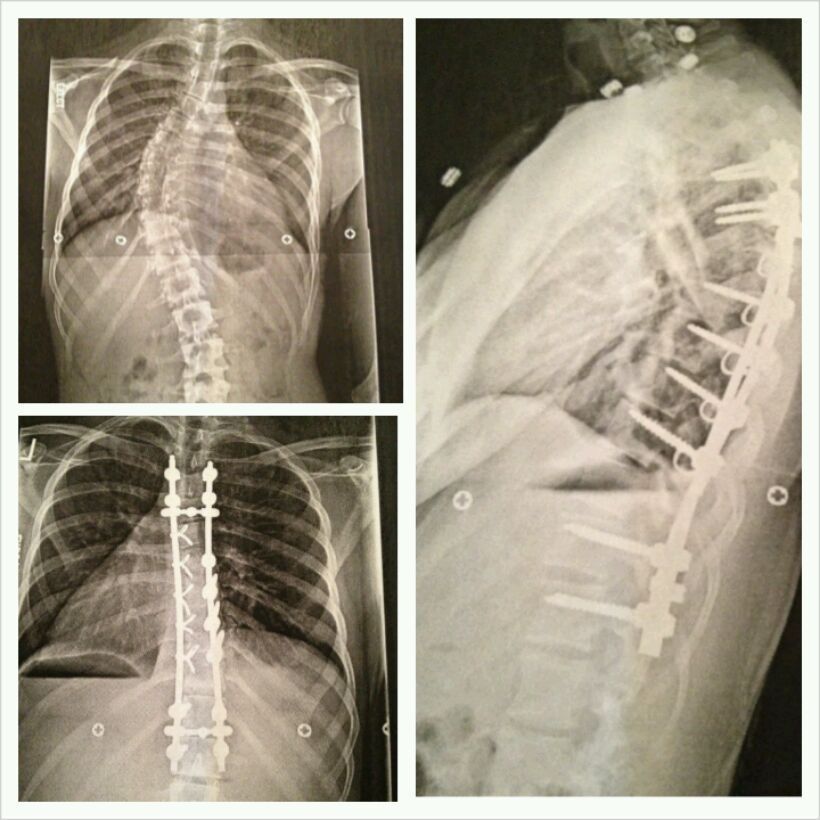

WOW!! Ghostv2, I'm sorry about your back, man is that bad!!

I wondered why this thread was 2 pages and I completely understand your situation now. That was some major back surgery there!! Your probably an inch taller now. I hope you can enjoy some pain free years.......